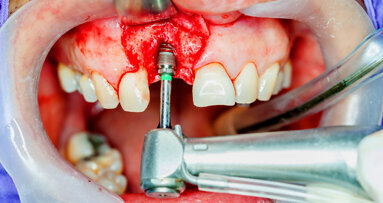

An atraumatic extraction protocol was used, involving initial luxation with a periotome and a rotational rather than facial-palatal method of displacement, thereby preserving the facial plate. Once the tooth had been extracted, a sub-sulcular envelope incision was used to gain access to the lesion, and the cyst was enucleated and the surrounding bone curetted and decontaminated (Fig. 5). A surgical guide was used to ensure the optimal position of the implant (Fig. 6), and the apical cutting threads of the PrimeTaper EV implant (Fig. 7) ensured that the implant engaged effectively with the apical bone, but the insertion torque only reached 20 Ncm owing to the large cyst-related cavity and the resulting lack of significant initial bone-to-implant contact. The baseline ISQ value was 61 and 65 in the facial-palatal and mesiodistal directions, respectively (Fig. 8), but in my experience, this combination of torque and ISQ value indicated that the implant was suitable for immediate loading, since the torque was ≥ 20 Ncm and the ISQ value was ≥ 65 in one direction.

Fig. 7: View of the implant passing across the infra-bony cavity.